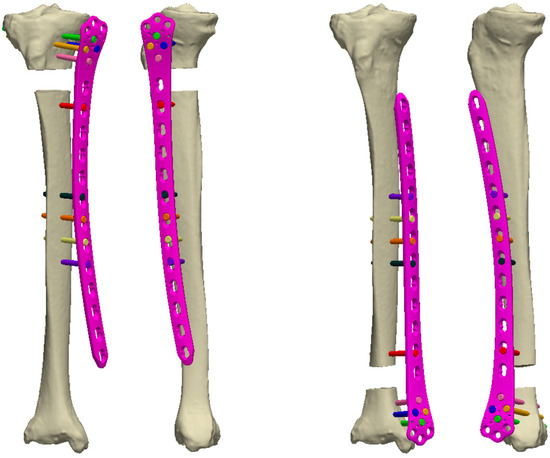

Single-Stage Externalized Locked Plating for Treatment of Unstable Meta-Diaphyseal Tibial Fractures

by Biser Makelov, Dominic Mischler, Peter Varga, Theerachai Apivatthakakul, James W. A. Fletcher, Deyan Veselinov, Till Berk, Dimitur Raykov and Boyko Gueorguiev

J. Clin. Med. 2023, 12(4), 1600; https://doi.org/10.3390/jcm12041600 - 17 Feb 2023

Cited by 3 | Viewed by 4965

(1) Background: Unstable meta-diaphyseal tibial fractures represent a heterogeneous group of injuries. Recently, good clinical results have been reported when applying a technique of externalized locked plating in appropriate cases, highlighting its advantage in terms of less additional tissue injury compared with conventional [...] Read more.

(1) Background: Unstable meta-diaphyseal tibial fractures represent a heterogeneous group of injuries. Recently, good clinical results have been reported when applying a technique of externalized locked plating in appropriate cases, highlighting its advantage in terms of less additional tissue injury compared with conventional methods of fracture fixation. The aims of this prospective clinical cohort study were, firstly, to investigate the biomechanical and clinical feasibility and, secondly, to evaluate the clinical and functional outcomes of single-stage externalized locked plating for treatment of unstable, proximal (intra- and extra-articular) and distal (extra-articular), meta-diaphyseal tibial fractures. (2) Methods: Patients, who matched the inclusion criteria of sustaining a high-energy unstable meta-diaphyseal tibial fracture, were identified prospectively for single-stage externalized locked plating at a single trauma hospital in the period from April 2013 to December 2022. (3) Results: Eighteen patients were included in the study. Average follow-up was 21.4 ± 12.3 months, with 94% of the fractures healing without complications. The healing time was 21.1 ± 4.6 weeks, being significantly shorter for patients with proximal extra- versus intra-articular meta-diaphyseal tibial fractures, p = 0.04. Good and excellent functional outcomes in terms of HSS and AOFAS scores, and knee and ankle joints range of motion were observed among all patients, with no registered implant breakage, deep infection, and non-union. (4) Conclusions: Single-stage externalized locked plating of unstable meta-diaphyseal tibial fractures provides adequate stability of fixation with promising clinical results and represents an attractive alternative to the conventional methods of external fixation when inclusion criteria and rehabilitation protocol are strictly followed. Further experimental studies and randomized multicentric clinical trials with larger series of patients are necessary to pave the way of its use in clinical practice. Full article

(This article belongs to the Section Orthopedics)

Show Figures

Figure 1